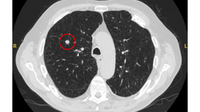

Computed tomography (CT) showing two areas (red circles) of mucoid impaction of the left upper lobe subsegmental bronchi, resulting in appearance that mimics a nodule

From the collection of Dr George Tsaknis, MD, PhD, FRCP(London), MRQA, MAcadMEd, PGCert; used with permission